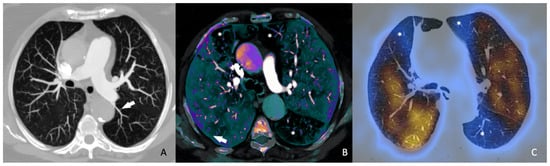

Conversely, the meta-analysis by Meinel et al. [13], published in 2015, reviewed 49 studies involving 13,162 patients and concluded that the axial RV/LV ratio should be included in all reports (Figure 1). An axial RV/LV ratio greater than 1 is associated with a 2.5-fold higher risk of all-cause mortality and adverse outcomes, and a 5-fold higher risk of PE-related mortality. This finding contrasts with the results of Kang et al., as we have previously mentioned, since this author asserts that this datum is not a predictor of adverse effects. However, Meinel et al. provide a detailed analysis of the relationship between the axial RV/LV diameter ratio and the all-cause mortality risk, stratified by sources of heterogeneity, resulting in a robust conclusion. In clinical practice, especially in the urgent context where CTPA studies are conducted, the ratio of the right ventricular diameter to that of the left is a measure that is easy to obtain, unlike ventricular volumes or four-chamber reconstructions. Therefore, Meinel’s recommendation is deemed appropriate. While the parameters suggested by Kang et al. are undeniably valuable, their acquisition post-acute event requires practice, time, and skill, which may not be feasible in emergency settings.

Figure 1. Fifty-six-year-old woman diagnosed with acute pulmonary thromboembolism, by axial CT angiography. (A). Axial RV/LV diameter ratio > 1 measured at the base of both ventricles (black arrows). (B). Filling defects in both main pulmonary arteries (*), with a saddle thrombus.